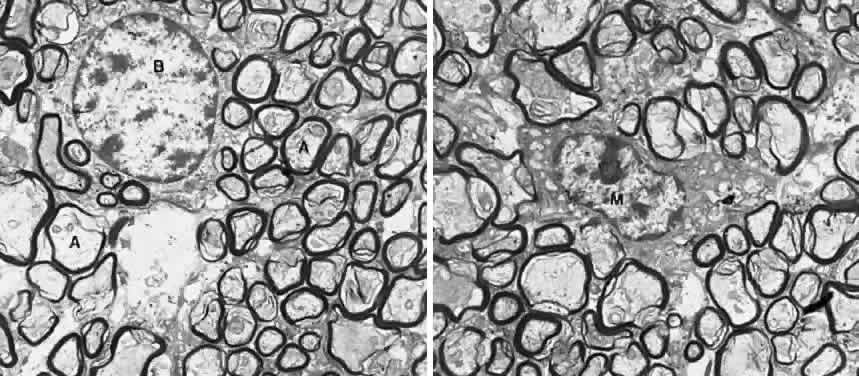

The axons, also called nerve fibers, are the major component of the optic nerve. The nonmyelinated axons of the retinal ganglion cells converge toward and turn sharply on the optic disc. Once they penetrate the lamina cribrosa, the axons immediately become myelinated (see Fig. 2). In cross-section using hematoxylin and eosin (H&E) stain, the principal myelinated optic nerve fibers appear as small, faintly stained, eosinophilic dots surrounded by relatively clear halos. These clear halos, representing the myelin sheaths, are the result of lipid dissolution during processing. Special stains can be used to enhance the appearance of axons (e.g., Bodian's method and Luxol fast blue staining). Under electron microscopy, the nerve fibers are identified as cytoplasm with mitochondria enveloped by multilaminar myelin sheaths. The myelin sheaths of the optic nerve are formed by oligodendrocytes (Fig. 3). A distinct arrangement of axons is found in the optic nerve: the peripheral retinal axons are located in the peripheral portion of the optic nerve, and the central area of the nerve contains fibers from the posterior retina. Macular fibers form the papillomacular bundle and enter the disc temporally; they remain temporal for a short distance behind the eye, but as they proceed further posteriorly these fibers become diffusely distributed. Nerve fibers arising in the nasal half of the retina cross in the chiasm; axons arising in the temporal half are uncrossed.11 It is believed that most optic nerve fibers carry afferent visual and pupillomotor impulses. A few fibers project to the hypothalamus or superior colliculus, where they may provide afferent information affecting the body's circadian rhythm or a rudimentary representation of the visual space (blindsight), respectively.12,13 Efferent (centrifugal) fibers of the optic nerve, presumed to be vasomotor in function, were identified in the human optic nerve after enucleation of the globe. Silver staining of these axons showed retrograde degeneration, whereas the remaining axons in the orbital portion of the optic nerve showed little or no retrograde degeneration. In uninterrupted optic nerve, efferent axons could not be differentiated from those of the afferent type.14

Fig. 3. Ultrastructure of the optic nerve. (A) Axons are surrounded by myelinated sheath. (B) Oligodendritic cell. (M) Microglial cell. × 18,750. (Courtesy of Dr. John R. Guy)

OLIGODENDROCYTES. Oligodendrocytes can make and maintain myelin sheaths of the optic nerve axons, similar to the function of Schwann cells in the peripheral nerves, but without forming a basement membrane around the myelin sheaths.21 Oligodendrocytes are normally absent in the retina and optic nerve head, appearing posterior to the lamina cribrosa. Morphologically, they show small, round or oval nuclei, a granular cytoplasm, and delicate branching processes that terminate in loops. Oligodendrocytes are located in groups between the axons, usually near the center of the axonal bundles, with their processes running parallel to the axons. In contrast to the astrocytes, oligodendrocytes are devoid of footplates; they do not exhibit any connection with connective tissue septa, and they lack the ability to regenerate once injured.

When viewed by electron microscopy, oligodendrocytes appear moderately electron dense compared with astrocytes. The nucleus is round or oval and is usually eccentrically located, leaving a large mass of cytoplasm at one pole of the cell. The nuclear content exhibits a slight clumping of chromatin that appears as a rim beneath the nuclear envelope. The cytoplasm is rich in ribosomes, either free or associated with the endoplasmic reticulum. The Golgi complex is well developed. The oligodendrocytes have neither glycogen granules nor bundles of intermediate filaments (see Fig. 3). When analyzed by immunohistochemical methods, oligodendrocytes stain negative for GFAP but positive for galactocerebroside, myelin basic protein, and neural cell marker HNK-1/N-CAM.5